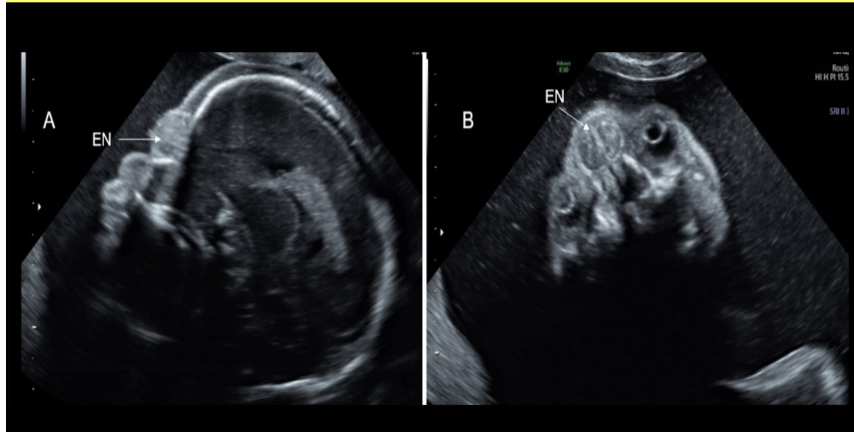

the cerebellum shows what sono sign

b) banana sign